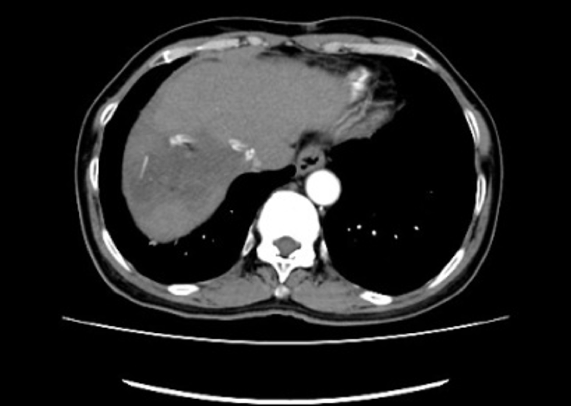

术后2021年12月13日行复查上腹部CT平扫提示:1)右肝癌 TACE 肝复发肿瘤切除术后改变,现术区密度减低影并其内积气,建议增强检查;腹腔引流管置入后改变;2)原肝内散在低密度结节较前未见明显显示。肝硬化;3)新增腹腔多发渗出,建议随诊复查。新增腹壁皮下渗出改变、腹壁肿胀;4)胆囊未见具体显示;5)腰椎退变;6)扫及双侧胸腔积液;双肺多发密度增高影,建议完善胸部CT检查(图4)。

图4.2021年12月13日行复查上腹部CT